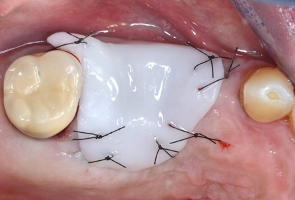

2. Εφαρμόστε το πολυμερές Elemental προσαρμοσμένο στην ανατομία του πεδίου. Το πολυμερές πήζει σε ένα άκαμπτο, σταθερό υλικό. Εάν η εφαρμογή δεν είναι σωστή, ξαναζεστάνετε και ξαναπλάστε το υλικό. Προαιρετικά, σταθεροποιήστε το Elemental με ένα χιαστί ράμμα. Αυτό δεν είναι απαραίτητο σε μονήρεις περιοχές, όπου μπορείτε να επιτύχετε μηχανική συγκράτηση στα διπλανά δόντια.

3. Το Elemental θα κρατήσει το οστικό μόσχευμα στη θέση του και θα προωθήσει το σχηματισμό κοκκιώδους ιστού. Δε απαιτείται η χρήση επιπρόσθετης μεμβράνης. Αφαιρέστε το υλικο μετά από 3-8 ημέρες, ανάλογα με τις διαστάσεις χειρουργικού πεδίου.